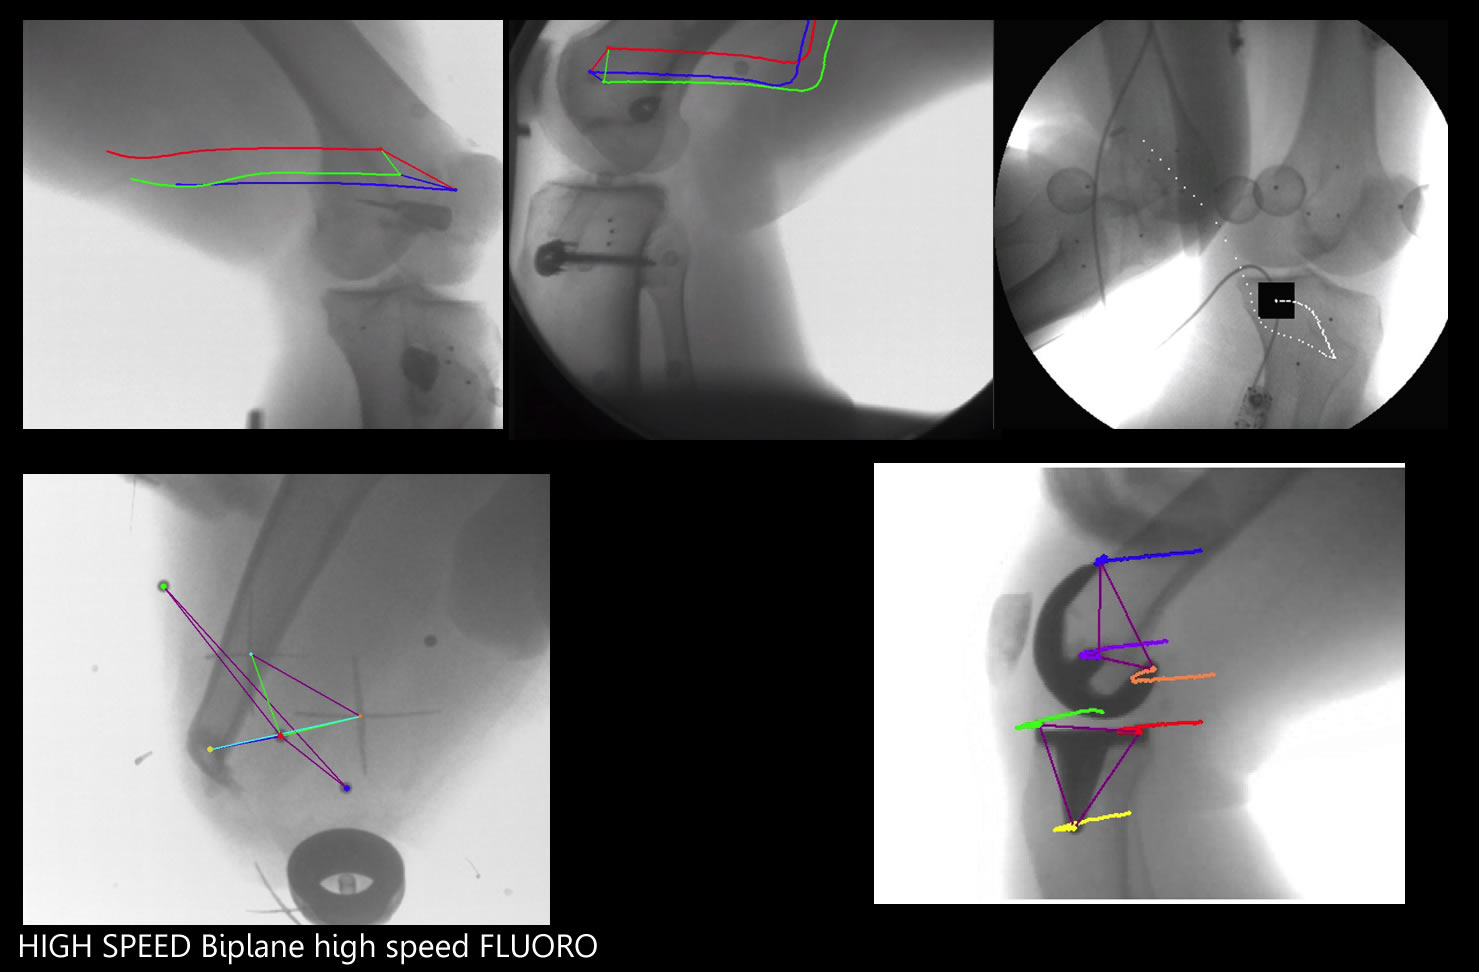

LOAD BEARING DYNAMIC IMAGING deformation scanner

Producing many different imaging modalities

Motion corrected 4D stereotactic CT Multi-axis 4D scanner-Fusion scanner